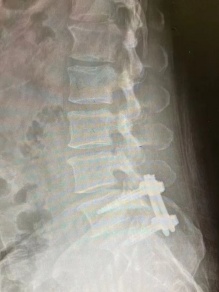

手术过程很顺利,精准定位之后,谢宁主任医师在病人腰部开了4个15mm的钥匙孔切口,手术操作全程在脊柱内镜下完成,放大20倍的影像把神经、血管看得一清二楚,手术工具都是毫米级的,对正常的肌肉几乎没有影响,精准的去除很少量骨质,摘除巨大脱出的腰椎间盘组织,出血几乎忽略不计。手术结束不放引流管,术后第2天下地,全程住院5天。术后3个月复查时,拍片显示植骨已经融合;小张健步如飞,又驰骋在篮球场上,他非常满意。

仅有4个15mm长的“钥匙孔”切口

术后3个月复查的X线片